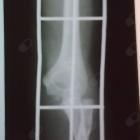

A cirurgia ainda é bastante recente, é normal ter edema, dor e limitações de movimentos. O mais importante é que esteja evoluindo sem sinais de infecção e com boa estabilidade da fixação.

Normalmente a incisão (corte) para a retirada da placa é a mesma que a utilizada para a cirurgia

Se o implannte soltar ou ferir a pele anos após a cirurgia tem Indicação de ser retirado.